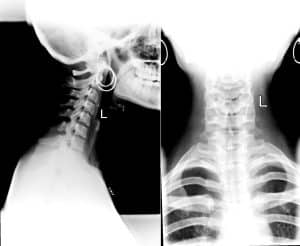

- X-ray examinations of the cervical vertebrae to determine if there are breaks or cracks.

According to USC Spine, a cervical fracture is a broken bone in the cervical region of the spine. A cervical dislocation is a ligament injury in the neck where “two (or more) of the adjoining spine bones have become abnormally separated from each other, causing instability.”

According to Medical News Today, the neck consists of seven small bones known as cervical vertebrae. The bones of the neck are found at the base of the skull and on top of the shoulders. A broken cervical vertebra is called a cervical fracture – or, in layman’s terms – a broken neck. If the break causes damage to the spinal cord or nerves, a nursing home resident can suffer paralysis or death. If there is no spinal cord damage, the resident may recover with proper orthopedic care.